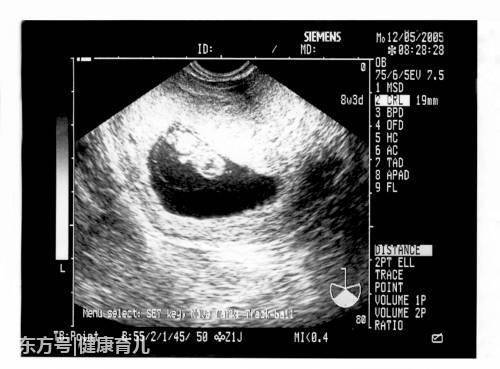

1、孕囊大小看胎儿性别

有传言说,如果孕囊大小的长和宽的相差在一倍以上,那么男宝宝可能性大。长和宽相等,或者相差不大的话,很可能是个女宝宝。有妈妈回顾起当年怀孕时的B超数据,来验证了一下,比如有位妈妈在怀孕8周时,孕囊大小是16mm×17mm,结果生下了一位小公主。

2、孕囊形状看胎儿性别

有人认为,孕囊形状可以看出胎儿是男是女。一般说来,如果孕囊的形状像茄子,或者是呈长条状的,则怀上男宝宝的可能性大;而如果孕囊是椭圆形或圆形的,那么很可能就是个女宝宝了。

3、胎心, 140以下男孩可能性大!150以上女孩可能性大!双顶径减股骨长,大于2.1是男孩,反之是女孩。